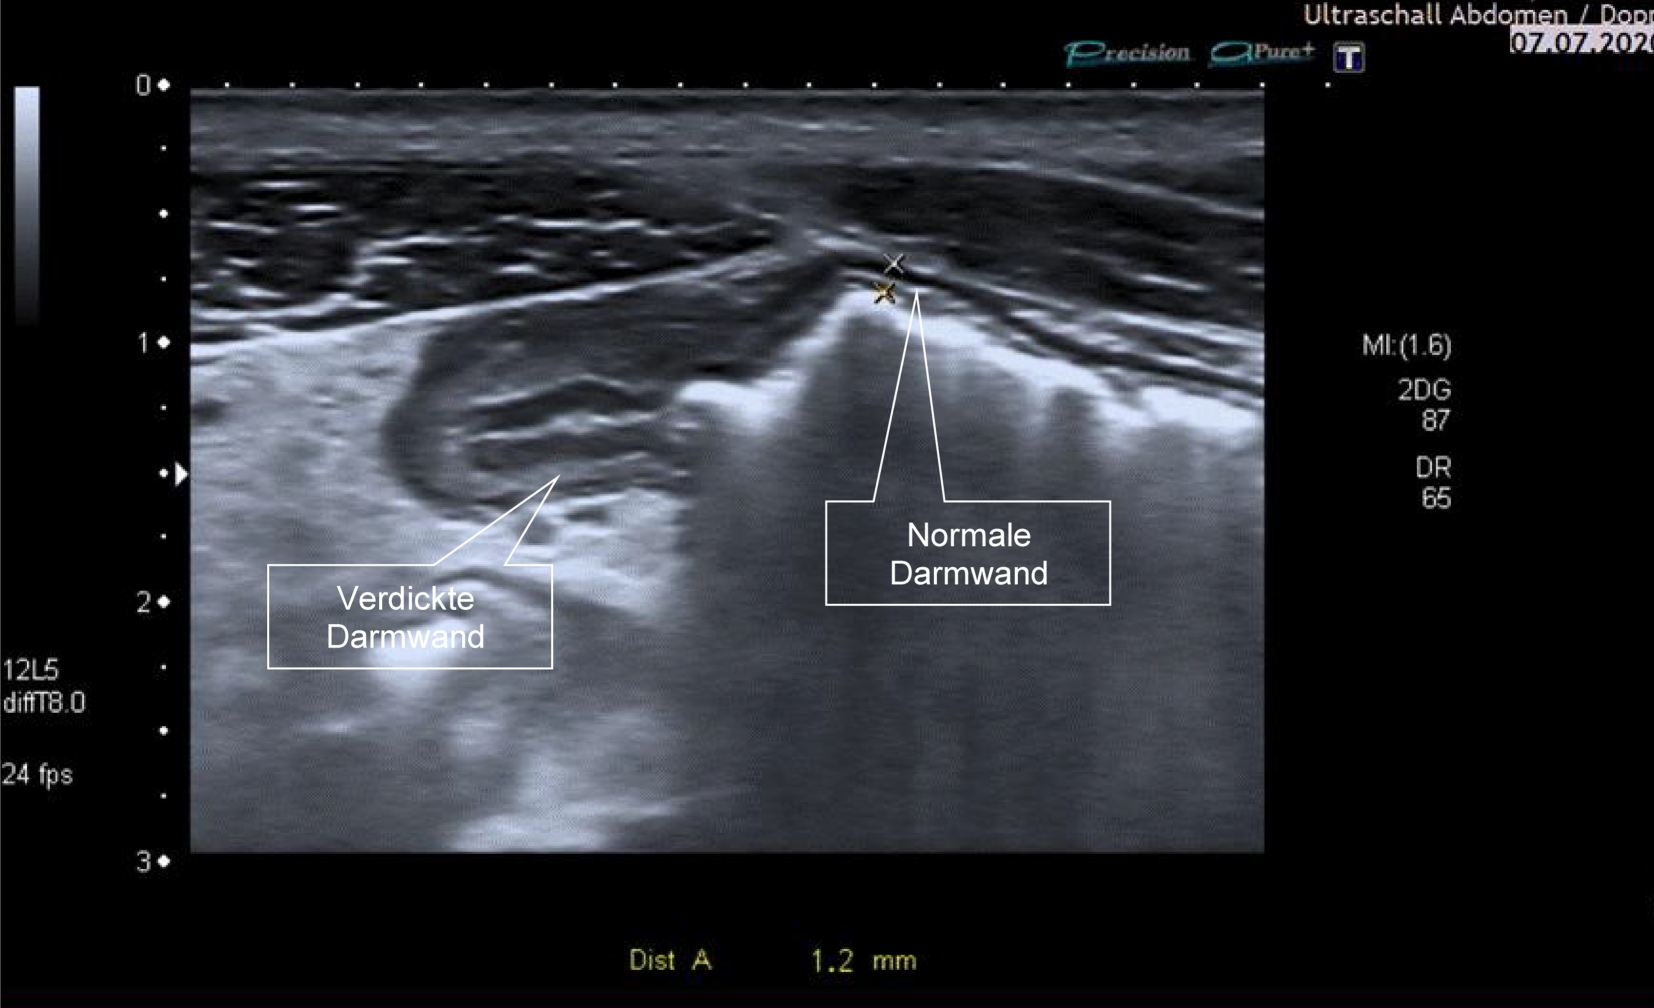

Der Darmultraschall ist aufgrund seiner einfachen Wiederholbarkeit und Verfügbarkeit auch hervorragend geeignet, das Therapieansprechen oder gegebenenfalls das Auftreten eines Rezidivs nach chirurgischen Resektionen zu detektieren. Der Ultraschall mit Kontrastmittel weist eine sehr gute Korrelation mit dem postoperativen endoskopischen Rutgeerts-Score auf (Abb. 3 und 4).

Abb. 3

43-jähriger Patient mit langjährigem Morbus Crohn des Kolons. (Zuletzt seit 2 Jahren ohne Medikation, bei selbstständigem Absetzen von Ustekinumab. Seit 2 Wochen zunehmende Unterbauchschmerzen und intermittierend Fieber. Die Darmwand des Colon ascendens ist deutlich verdickt, sie ist echoarm als Zeichen der Entzündung. Die Schichtung ist aufgehoben, das Lumen ist komprimiert. Es zeigt sich eine mesenteriale Reaktion im Sinne einer echoreichen Gewebevermehrung um das Kolon. In diesem Bereich dunkle Areale: Fisteln, die vom Kolon ausgehen und zu drei kleinen Abszessen geführt haben)

Abb. 4

Derselbe Patient, Darstellung mit dem 10-MHz-Schallkopf. Deutlich lässt sich ein Abszess im mesenterialen Gewebe abgrenzen (Pfeil). Zudem zeigt sich parakolisch freie Flüssigkeit